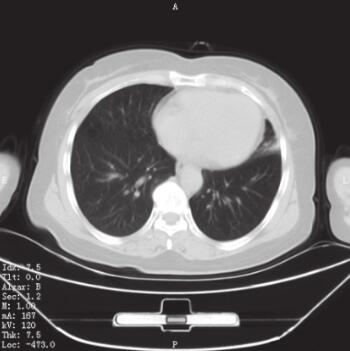

入院后检查:生命体征平稳,慢性病容,呼吸急促,口唇及甲床不发绀。上肺部可闻及双相哮鸣音,以吸气相为主,心率90次/分,律齐,各瓣膜听诊区未闻及杂音,肝脏、脾脏在肋缘下未能触及,剑突下无压痛,双下肢不水肿。血常规:WBC 7.66×109/L,N% 75.0%,HGB 135g/L,PLT 290×109/L。红细胞沉降率23mm/h。肝肾功能、生化未见异常。血气分析提示:pH 7.42,PaO2 80mmHg(1mmHg=0.133kPa),PaCO2 38mmHg。凝血指标及D-Dimer定量检测均在正常范围。入院后复查肺部CT(图1)。

图1 入院后肺部CT表现

A.隆突下肺窗显示隆突稍增宽;B.肺窗显示左肺舌叶炎性改变;C.隆突下纵隔窗显示隆突稍增宽

CT报告为左肺舌叶炎性改变,未见明确的占位性病变,考虑患者无咳痰,体温正常,血常规正常,无临床感染依据,未给予抗感染治疗,与家属进行沟通后决定完善电子支气管镜检查并在左主支气管新生物处取得病理组织。

5. 气管镜检查确诊后再次复习肺部CT表现,发现隆突较正常水平稍有增宽。本患者经过气管镜检查最终得到了确诊,但是家属拒绝进一步诊治使我们感到遗憾。